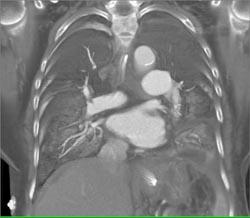

Neurogenic Sarcoma